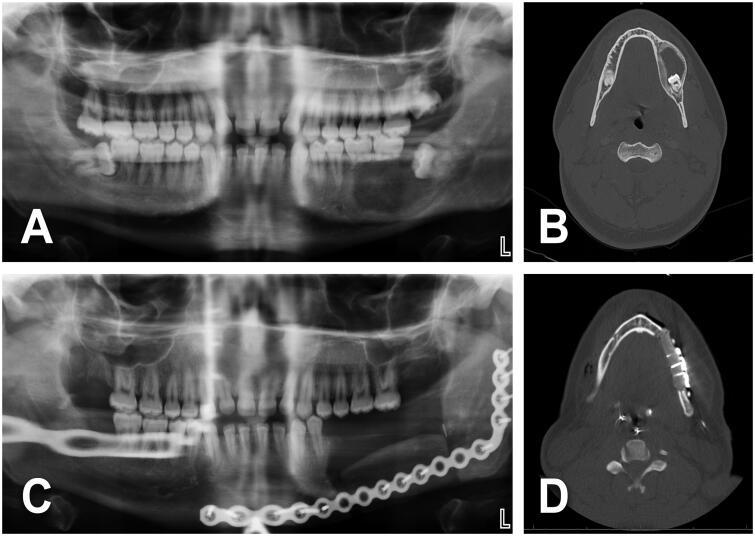

We studied 21 patients who underwent radical ameloblastoma excision followed by immediate reconstruction. Comorbidities, consumption of alcohol and/or tobacco and BMI status did not contribute to an unfavorable outcome. Giant ameloblastoma (≥5 cm) and/or tumor involving bony curvatures increased surgical complexity, the incidence of complications and hospital stay.

我们研究了21例接受成釉细胞瘤根治性切除并立即进行重建的患者。合并症、酒精和/或烟草消费以及体重指数状况并未导致不良预后。巨大成釉细胞瘤(≥5厘米)和/或累及骨弯曲的肿瘤增加了手术复杂性、并发症发生率和住院时间。